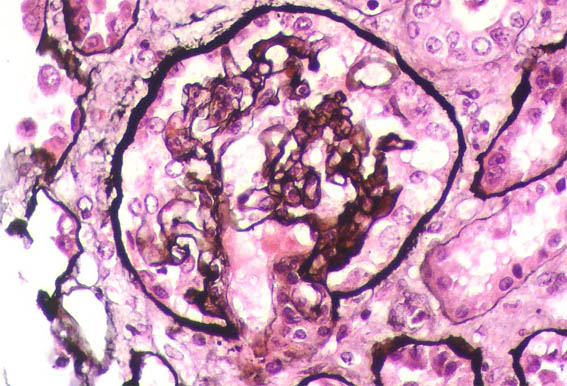

Figure 4. Methenamine-silver, X400.